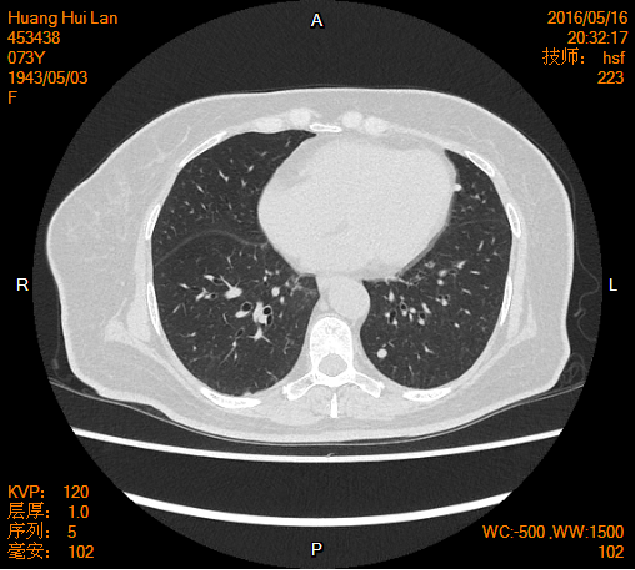

2016-04-13胸腹盆CT

2016-05-17胸腹盆CT(术后基线)